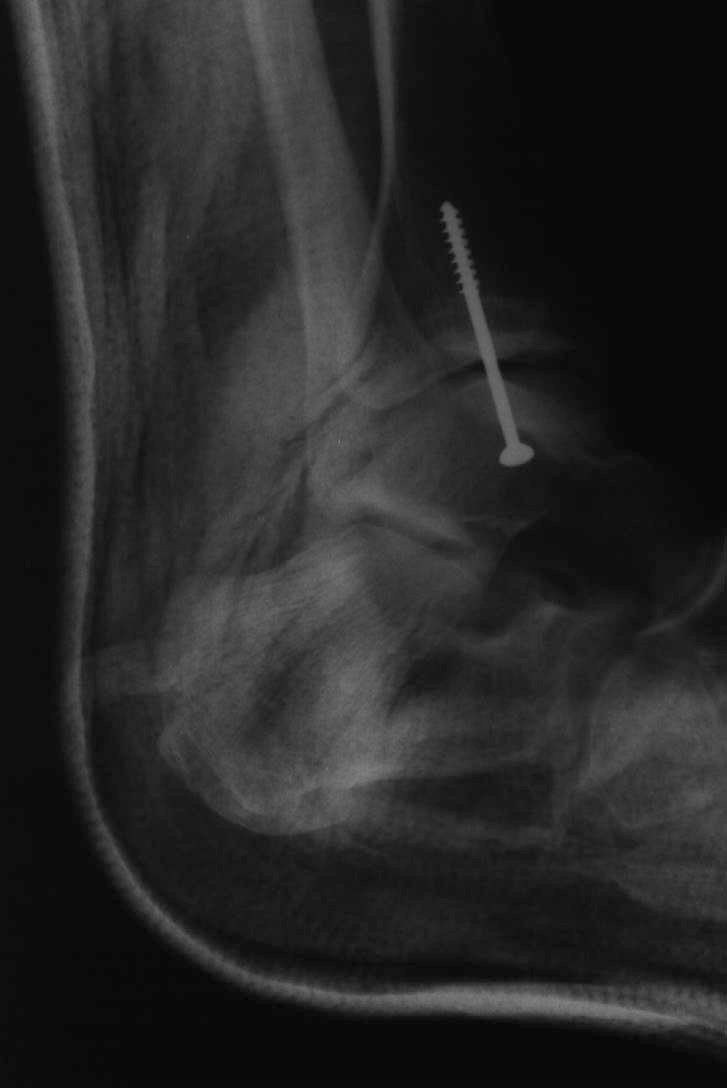

"Meanwhile, back on the route, Steph had decided to make the move, which involved reaching her right hand up to the left arete of the slab and, of course, the inevitable barndoor occurred. She pivoted balletically round the arete to fall down the other face, completely missing the expertly placed spotters and landing on the less well placed boulders below. She landed on her ankle and taken a slice off it against a rock which had also broken the bone and gouged it a bit. After convincing her that passing out was a bad idea we eventually managed to fireman's lift her to the car and the hospital where she had her ankle 'pinned'. As the x-ray shows it would have been more appropriate to call it 'screwed'."

Before having the pin After Side view with pin